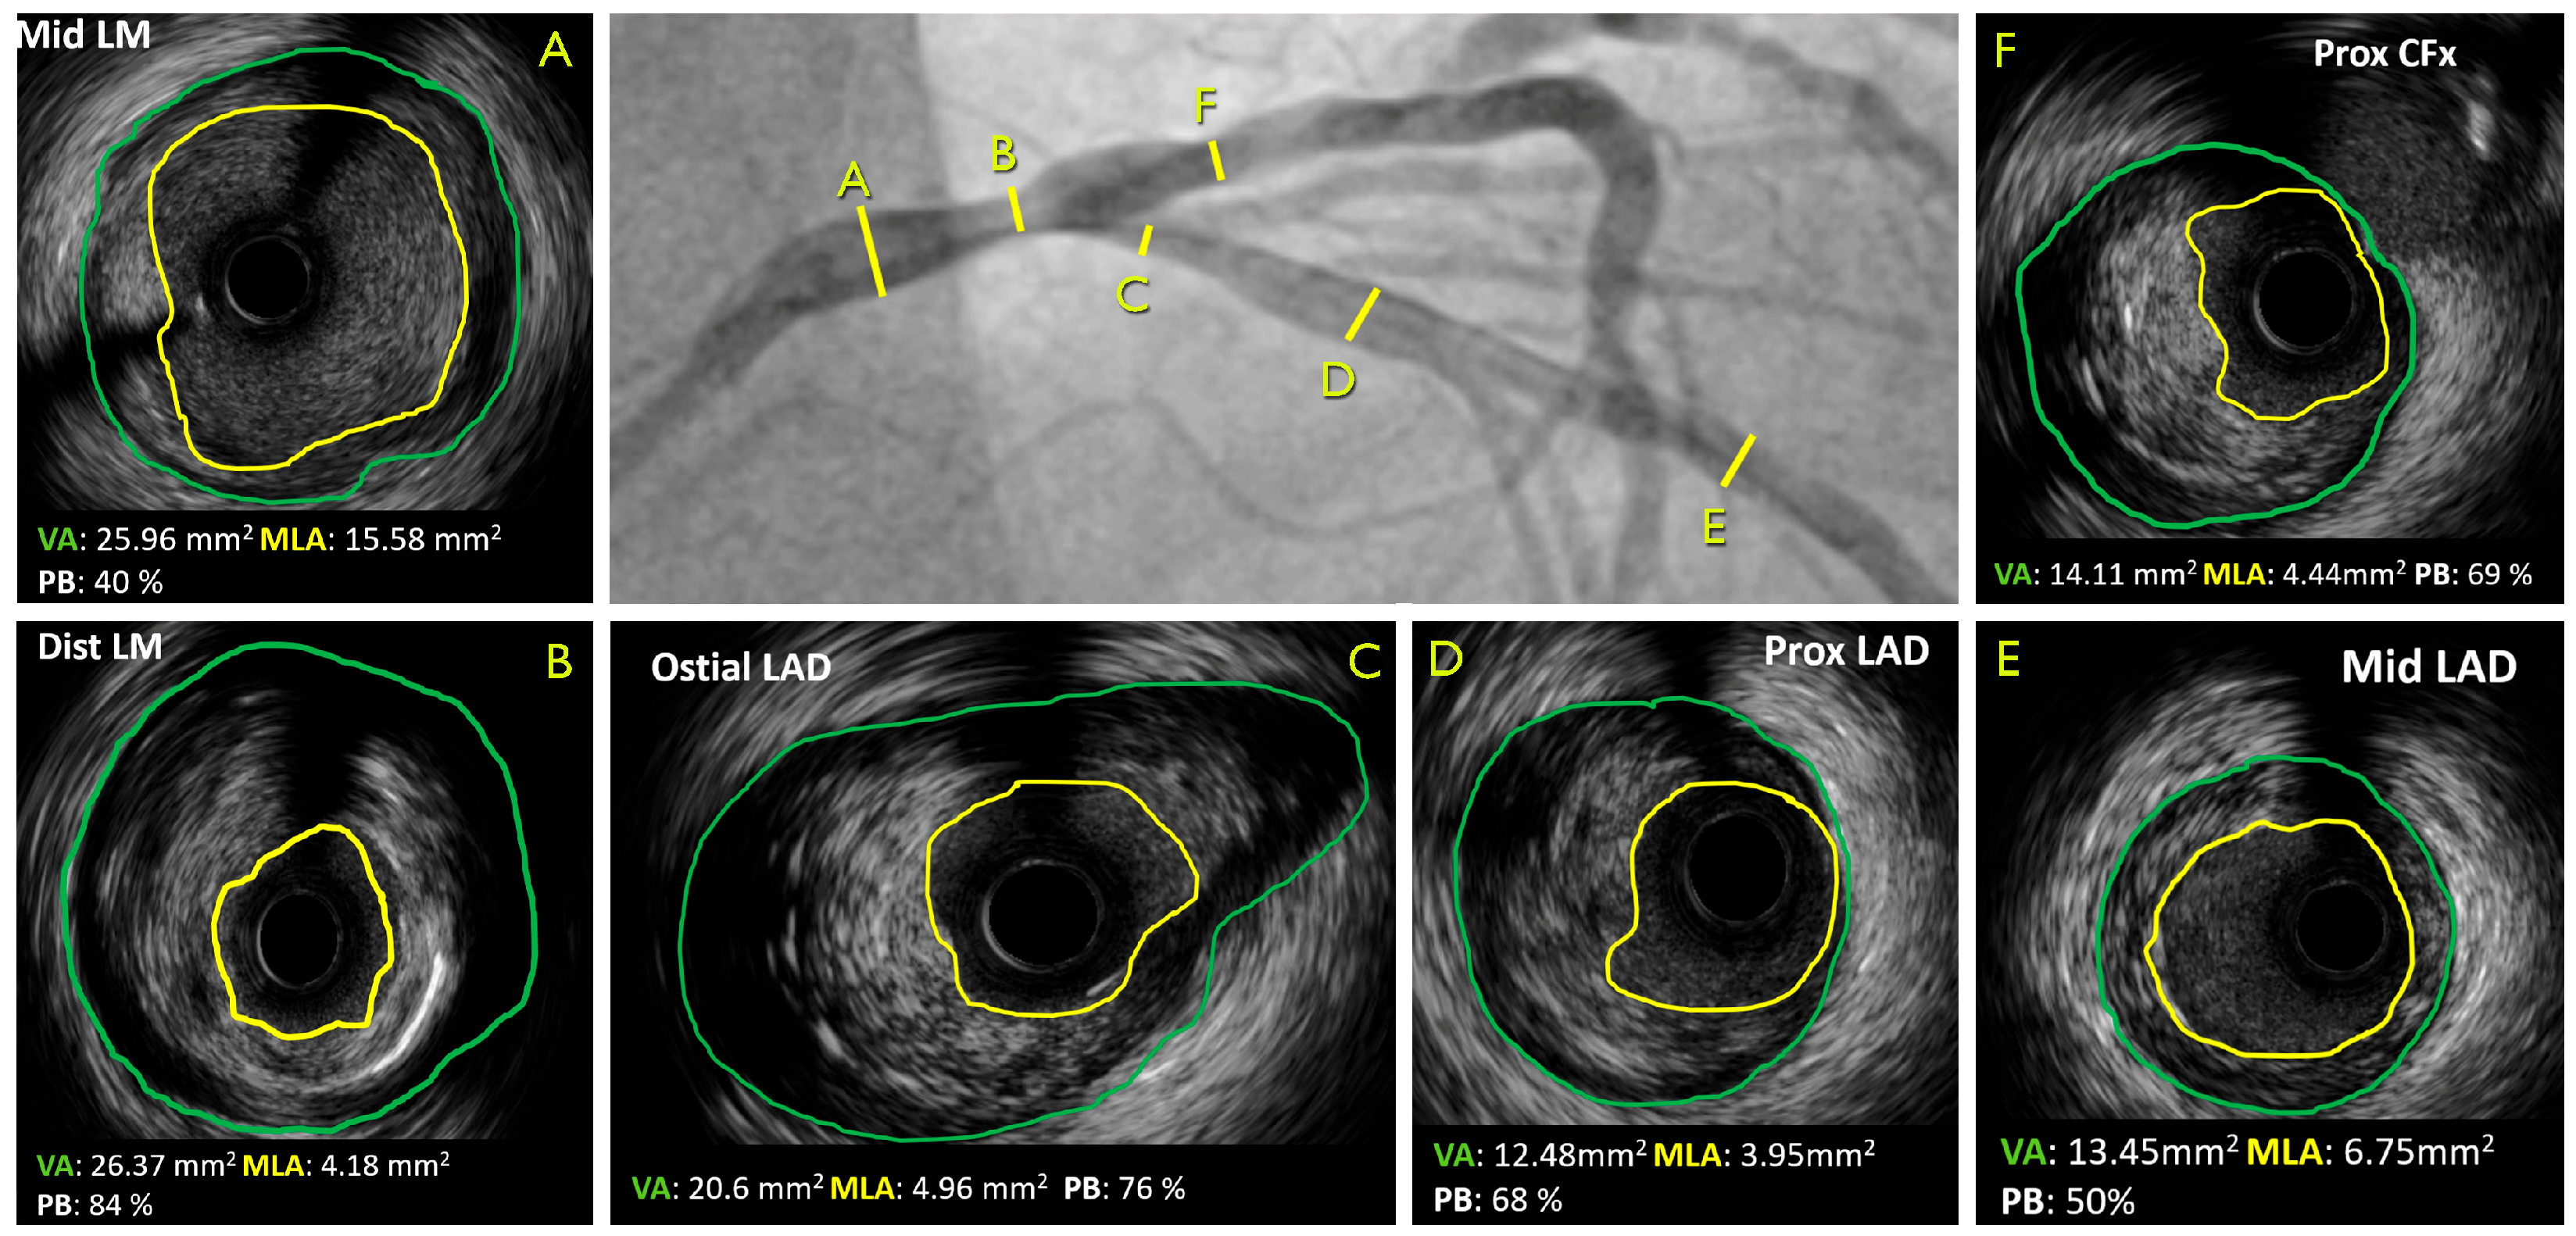

- Andreini, D.; Collet, C.; Leipsic, J.; Nieman, K.; Bittencurt, M.; De Mey, J.; Buls, N.; Onuma, Y.; Mushtaq, S.; Conte, E.; et al. Pre-procedural planning of coronary revascularization by cardiac computed tomography: An expert consensus document of the Society of Cardiovascular Computed Tomography. J. Cardiovasc. Comput. Tomogr. 2022, 16, 558–572. [Google Scholar] [CrossRef] [PubMed]

- Tajima, A.; Bouisset, F.; Ohashi, H.; Sakai, K.; Mizukami, T.; Rizzini, M.L.; Gallo, D.; Chiastra, C.; Morbiducci, U.; Ali, Z.A.; et al. Advanced CT Imaging for the Assessment of Calcific Coronary Artery Disease and PCI Planning. J. Soc. Cardiovasc. Angiogr. Interv. 2024, 3, 101299. [Google Scholar] [CrossRef]